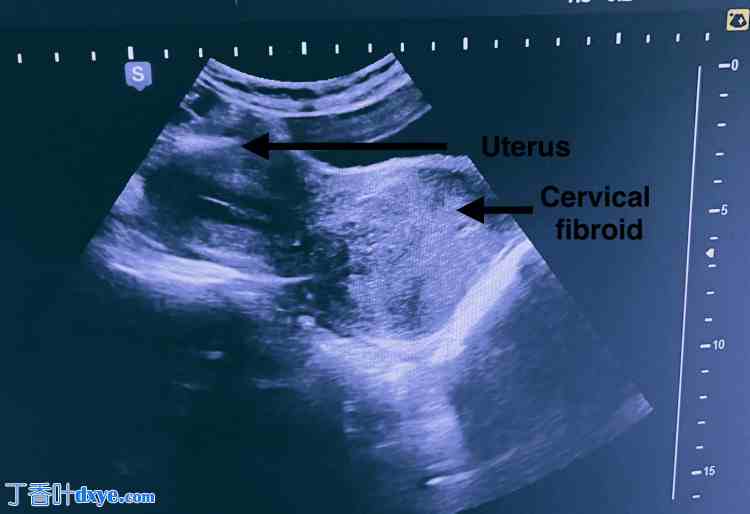

一名32岁、未生育(P0L0)的女性,因异常子宫出血伴腹部隐痛6个月入院。既往病史及手术史均无特殊。腹部柔软,无压痛,未触及腹盆腔肿块。窥器检查发现宫颈前唇增厚,血流丰富。双合诊发现宫颈前部有一6×7厘米的肿块,向上延伸至子宫体部,上缘无法触及。超声检查显示子宫大小正常,前倾,子宫内膜厚度为7.5毫米。子宫下段及宫颈可见一边界清晰的异质性病灶,大小为5.3×6.3×5.6厘米,血流丰富;初步诊断为宫颈肌瘤(?)癌(图 9)。双侧附件正常,未见游离液体。

图 9. 超声图像显示子宫大小正常,子宫下段及宫颈处可见边界清晰的异质性病变,大小为 5.3 x 6.3 x 5.6 cm,初步诊断为宫颈肌瘤。